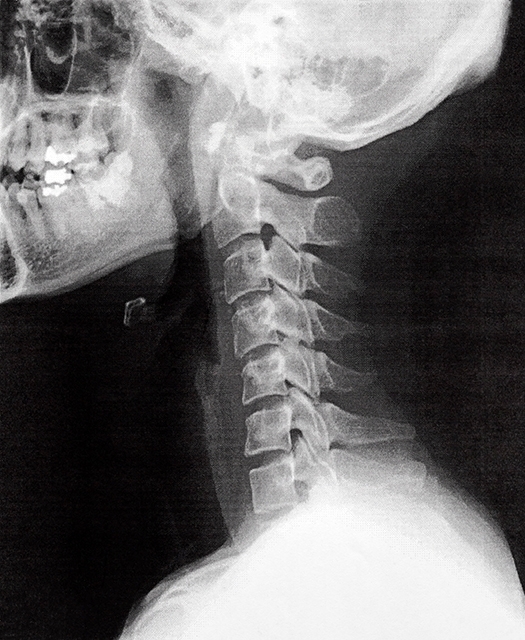

ストレートネックとは、本来あるべき頚椎(首の骨)の前弯(前カーブ)が減少してしまった状態をいいます。

ストレートネックを専門的に言い換えると「頚椎の前弯の減少」となります。

下記の写真のような状態です↓

上記の写真では本来あるべき頚椎の前弯がなくなり、頸椎のならびがストレートになっています。